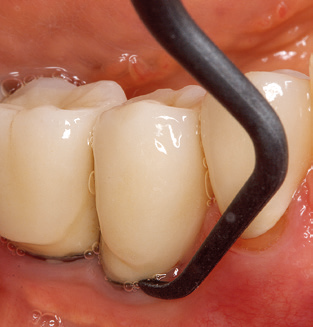

Abb. 4: Für das Sondieren an dentalen Implantaten sind biegsame, millimeterskalierte Sonden empfehlenswert (z.B. Colorvue Kit PCV11KIT6, Hu-Friedy). – Abb. 5a und b: Eine gerade Arbeitsspitze (1P, W&H Dentalwerk Bürmoos GmbH) ist universell für die Instrumentierung natürlicher Zähne geeignet. – Abb. 6: Für die Bearbeitung schwer zugänglicher Bereiche der Zahn- und Wurzeloberflächen (z.B. Furkationen) bieten sich gebogene Arbeitsspitzen (3Pr/3Pl, W&H Dentalwerk Bürmoos GmbH) an. – Abb. 7: Die spitz zulaufende sechseckige Implantatreinigungsspitze (1I, W&H Dentalwerk Bürmoos GmbH) ermöglicht eine atraumatische und effiziente Reinigung der Kronen- und Abutmentoberflächen. – Abb. 8: Für die manuelle Instrumentierung der Implantatoberflächen sind Titan- oder Carbonküretten geeignet.

Die gute Ausleuchtung des Arbeitsfeldes stellt eine wesentliche Erleichterung dar. Bei dem von den Autoren genutzten System ist dies gelungen, indem ein 5­facher LED­Ring in das Handstück integriert wurde. Natürlich werden für dieses System unterschiedliche Arbeitsspitzen für die jeweiligen Indikationsbereiche angeboten. Eine gerade, universell einsetzbare Spitze ist das Basisinstrument zur maschinellen Instrumentierung natürlicher Zähne (Abb. 5a und b). Für schwer zugängliche Bereiche im Seitenzahnbereich werden gebogene Spitzen angeboten, die auch einen Zugang zu freiliegenden Furkationen ermöglichen (Abb. 6).

Unerlässlich für die UPT implantat­ prothetisch versorgter Patienten sind natürlich Arbeitsspitzen für die Reini­gung von Implantatoberflächen. Der Implantatreinigungsaufsatz des hier verwendeten Systems zeichnet sich dabei durch eine spitz zulaufende sechskantige konische Form aus. Dieses Design erlaubt ein leichtes atraumatisches Eindringen in die periimplantäre Tasche und zeigt eine gute Reinigungsleistung (Abb. 7).